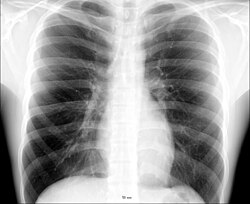

Koʻkrak qafasisudralib yuruvchilar, qushlar, sutemizuvchi hayvonlar va odamda toʻsh suyagi yordamida koʻkrak umurtqalariga qovurgʻalar birikishidan hosil boʻlgan bir butun tuzilma. Odamda koʻkrak qafasi yassi konusga oʻxshaydi. Koʻkrak qafasining yon, old va orqa devori bor. Yon va oldingi devorlari 12 juft qovurgʻadan hosil boʻladi. Oldinda qovurgʻalar uchi toʻsh suyagiga kelib taqaladi; orqa devorning oʻrtasi umurtqa pogʻonasining koʻkrak boʻlimidan iborat. Koʻkrak qafasining yuqorisidagi teshikdan koʻkrak boʻshligʻiga traxeya, qiziloʻngach, qon tomirlari va nervlar oʻtadi, pastdan diafragma chegaralab turadi. Koʻkrak qafasida oʻpka, yurak va tomirlar joylashgan. Nafas olganda koʻkrak qafasi kengayadi, ayni vaqtda boʻylama, old-orqa va koʻndalang hajmi kattalashadi. Koʻkrak qafasining hajmi va shakli yosh, jins va kasbga qarab turlicha. Koʻkrak qafasi chaqaloqlarda piramida shaklida, ayollarda pastki teshigi, boʻyi kaltaroq boʻladi.

Odamning umurtqa pog'onasida o'ttiz uchta umurtqa mavjud. Ko'krak qafasi TH1-TH12 bilan bog'langan. Qovurg'alar joylashishi va sternum bilan bog'lanishiga qarab tavsiflanadi. Barcha qovurg'alar orqada ko'krak umurtqalariga birikadi va mos ravishda birdan o'n ikkigacha raqamlanadi. To'g'ridan-to'g'ri sternum bilan bo'g'imga birikmaydiganlar qovurg'alar haqiqiy qovurg'alar, to'g'ridan-to'g'ri bo'g'im birikmaydiganlar esa soxta qovurg'alar deb ataladi. Soxta qovurg'alarga sternumga umuman biriktirilmagan suzuvchi qovurg'alar (o'n bir va o'n ikki) birikadi.